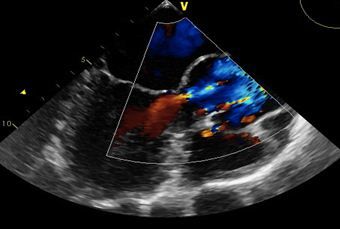

PFO can be detected in 10% to 15% of the population by transthoracic echocardiogram. Autopsy studies show a prevalence of PFO of approximately 26%.